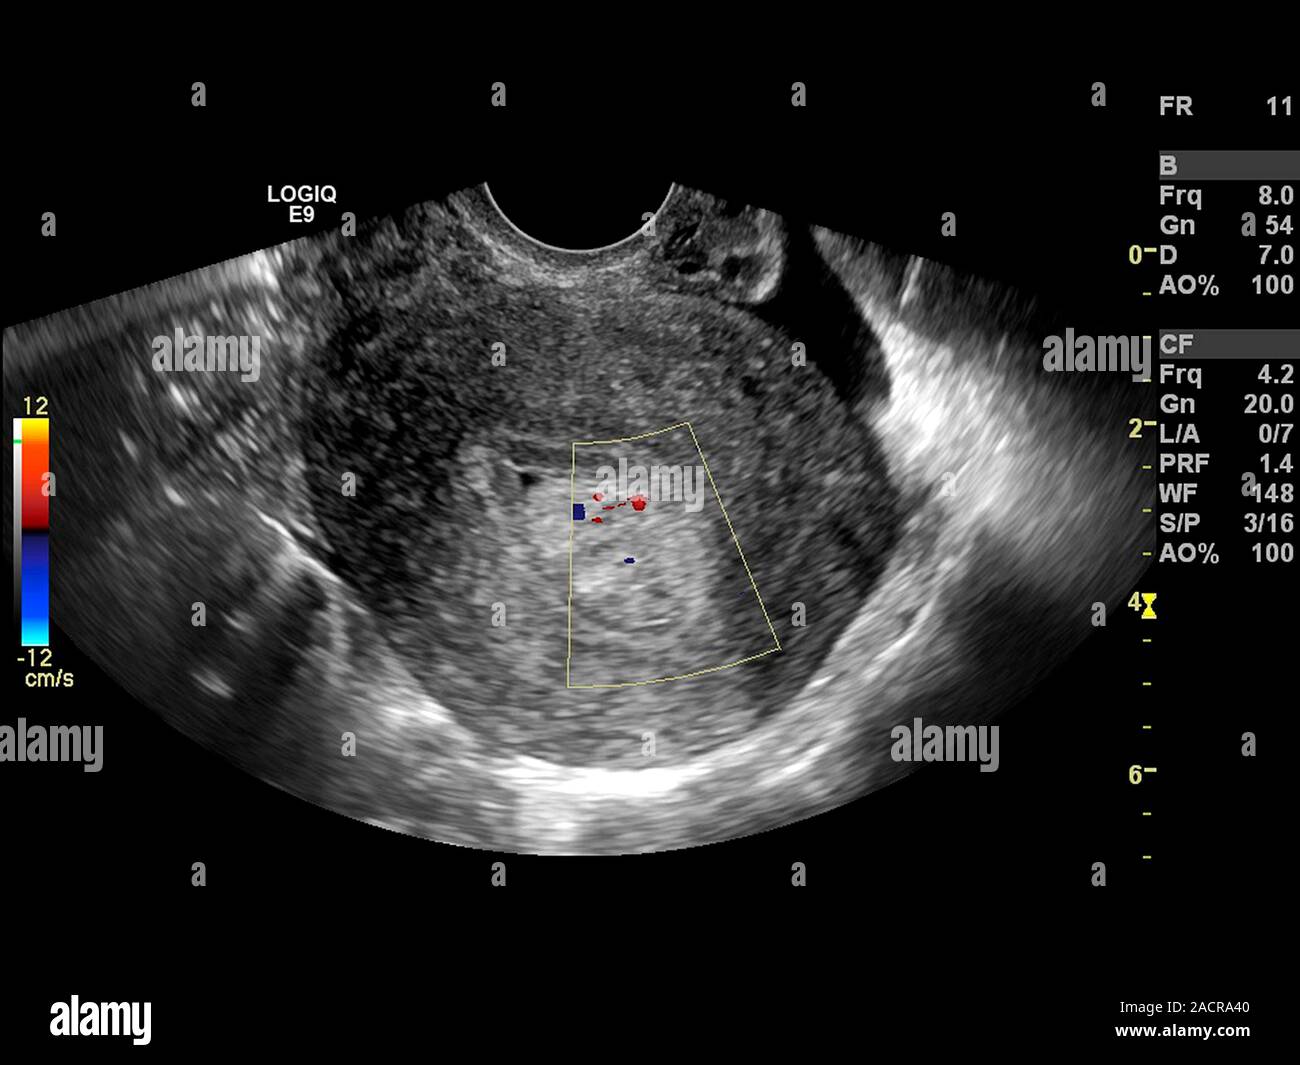

I polipi endometriali sono rilevabili durante esame obiettivo ginecologico solo in caso di sporgenza in vagina. Per questo motivo, in un contesto anamnestico compatibile, la diagnosi di poliposi viene posta attraverso l'ecografia transvaginale; questa metodica è in grado di individuare formazioni polipoidi singole o multiple e di misurarne le dimensioni. Nei casi sintomatici o laddove non è possibile distinguere la poliposi dall'iperplasia endometriale, l'ecografia deve essere seguita dall'isteroscopia, metodica che consente, attraverso biopsia, la caratterizzazione istologica dei polipi.